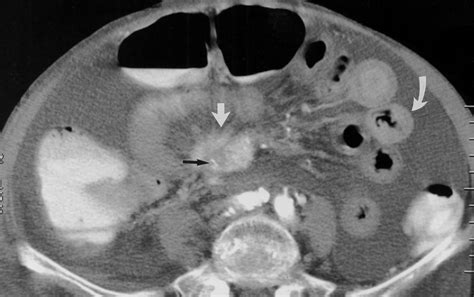

- Diverticulitis: Inflammation of small pouches (diverticula) in the colon wall often results in localized thickening in the affected area.

- bowel wall thickening on ct

- bowel wall thickening radiology